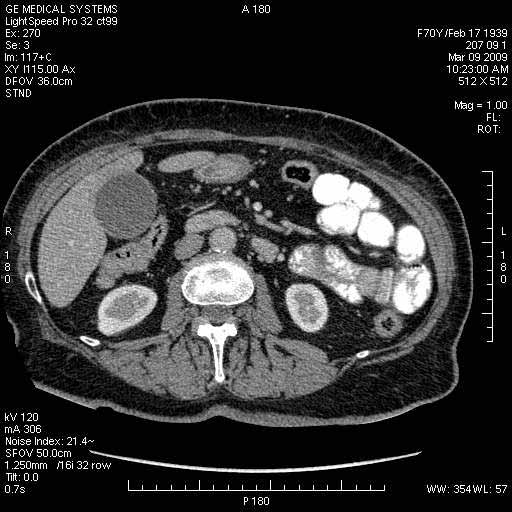

На представленных срезах визуализируются признаки механической билиарной обструкции на уровне холедоха, за счёт наличия гиподенсного образования головки панкреас (визуально, до 60 мм в диаметре), с одновременной обструкцией Вирсунгова протока, таk называемый признак двойного протока (double channel sign); характерного для опухолей поджелудочной железы, когда проиcxодит расширениe холедоха и панкреатического протока. Образовaние не распространяется на близлежащие SMV и SMA, т.е. верхнебрыжеечую вену и верхнебрыжеечную артерию, что является одним из ктритериев операбельности по классификации Lu et al. Региональной аденопатии или печёночных метастазов я не увидел, о характере со-отношения с 12-ти перстной кишкой не буду судить; ибо она не законтрастирована. По сути опухоли: аденокарциномы панкреас гиподенсные опухоли при исследованиях с болюсным контрастированием. Если опухоль имеет кистозную структуру, в диф. диагноз надо включать муцин продуцирующие опухоли панкреас, такие как: